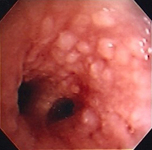

Трахеально-бронхеальный папилломатоз

Из коллекций Хосе Фернандо Сантакруза, дипломированного врача, члена Американской коллегии специалистов в области торакальной медицины, DAABIP, и Эрика Фолка, дипломированного врача, магистра наук; используется с разрешения